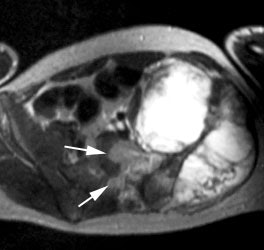

Ewings sarcoma of the pelvis: The bone scan demonstrates extensive, intense tracer uptake involving the left iliac wing, extending into the ischium and left sacrum. CT scan revealed a mixed, but predominantly sclerotic lesion involving the bone with an associated soft tissue mass. Note that the sacrum fails to demonstrate a CT abnormality. The T2 weighted images from the patients MR exam more clearly defines the lesion. Sacral involvement is clearly evident (white arrows) and there is also a large soft tissue component. |